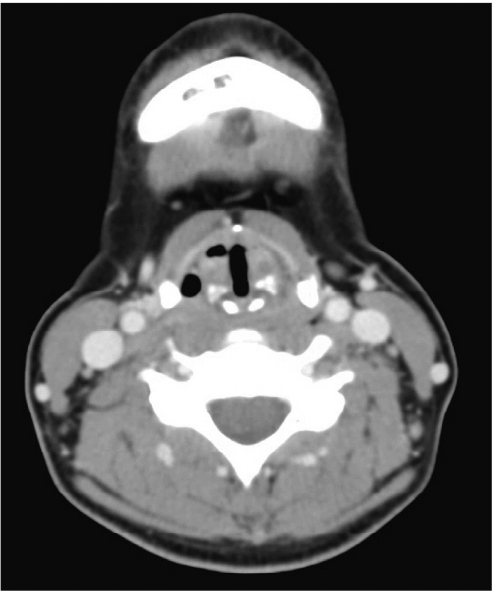

44 32 歳の女性。腹部膨満感を主訴に来院した。母親が慢性腎不全で血液透析を受 けている。両側季肋部から両側側腹部に腫瘤を触知し、軽度の圧痛を認める。血圧 146/92 mmHg。尿所見:蛋白案、潜血 安。血液生化学所見:尿素窒素 20 mg/dL、クレアチニン 1.2 mg/dL。左の側腹部の腹部超音波像別冊No. 8Aと腹 部 CT の冠状断像別冊No. 8Bとを別に示す。 次に行うべき検査はどれか。 (A)腎生検 (B) 頭部 MRA (C)排泄性尿路造影 (D) 下部消化管内視鏡 (E)ガリウムシンチグラフィ